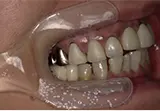

| 年齢/性別 | 70代女性 |

| 主訴 | 左下奥歯に痛みがある、全体的に治したい |

| 治療内容 | 全体的に歯周病やむし歯、根の治療を行い、仮歯を使用して咬合治療を実施。左上、右下、左下の計3本を抜歯し、右上には2本のインプラントを埋入しました。 |

| 治療期間 | 4か月(インプラントのみ) |

| 費用 | 1,116,500円税込 |

| リスク・副作用 | 炎症反応によって術後に腫れや副鼻腔炎が生じることがあります。その程度は、手術の範囲や方法によって異なりますが、多くの場合、時間の経過とともに徐々に治まります。 |